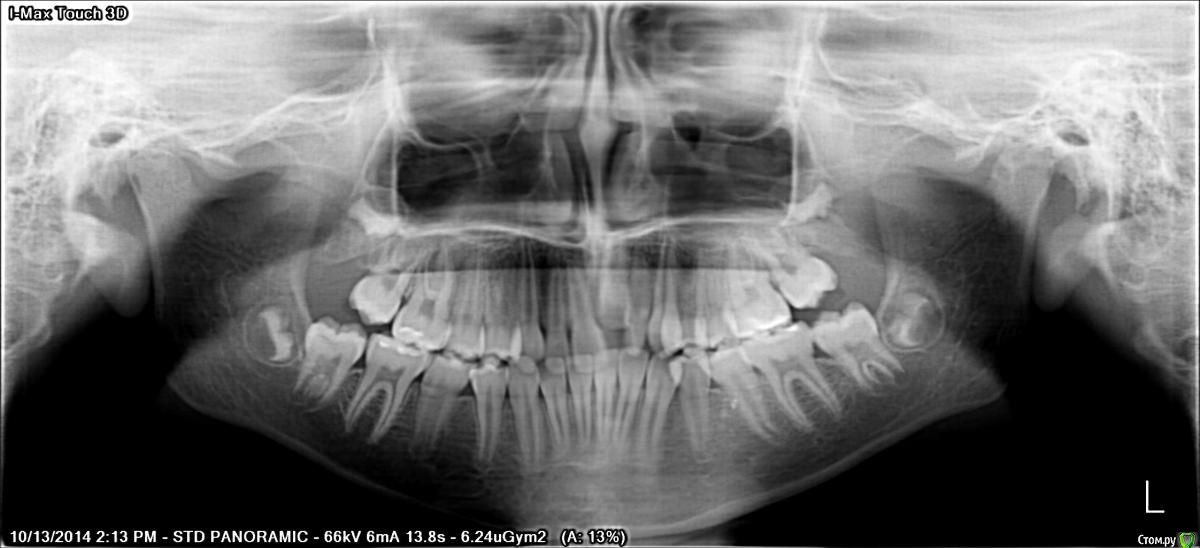

Серго Далакишвили Опубликовано 11 июня, 2016 Поделиться Опубликовано 11 июня, 2016 Здравствуйте, срочно нужен квалифицированный совет или указания.два года назад дочке поставили брикеты. ей сейчас двенадцать.место того чтоб всё исправить, всё испортили...у дочурки маленькая челюсть и врач начал расширять челюсти чтоб выиграть место.я конечно же не врач но я спросил ортодонта, может удалить четвёртый зуб появится места чтоб сдвинуть второй и третий к пятому зубу и потом спустим центральный зуб. короче конечно же меня некто не послушал и она(ортодонт) всё сделала по своему. итог. вместо того чтоб спустит один зуб подняли на верх остальные и не просто поднялись а очень....начала врач винить этот один зуб якобы это всё анкилоз.честно говоря врач в растерянности и когда я увидел её таким решил проконсультироваться у других врачей тоже.с начало сняли КТ и тут появляется самое плохое фактический кость разрушено на нескольких зубов верхней челюсти.а на нижней челюсти передняя шестёрка на столько наклонили в перёд что почти держатся на кончиках и нижней левой шестёрки виден корень.врачи посоветовали снят. брикеты дать восстановится костной ткани.люди добрые посоветуйте что делать, боюсь что если долнейшие действия будут не правильными дочка потеряет одного зуба остальные зубы.прилагаю панорамные снимки до и после, и ссылку на КТ можно скачать через www.dropbox.com https://www.dropbox.com/s/l7s5zqa777hsr70/Romexis.exe?dl=0 Ссылка на комментарий